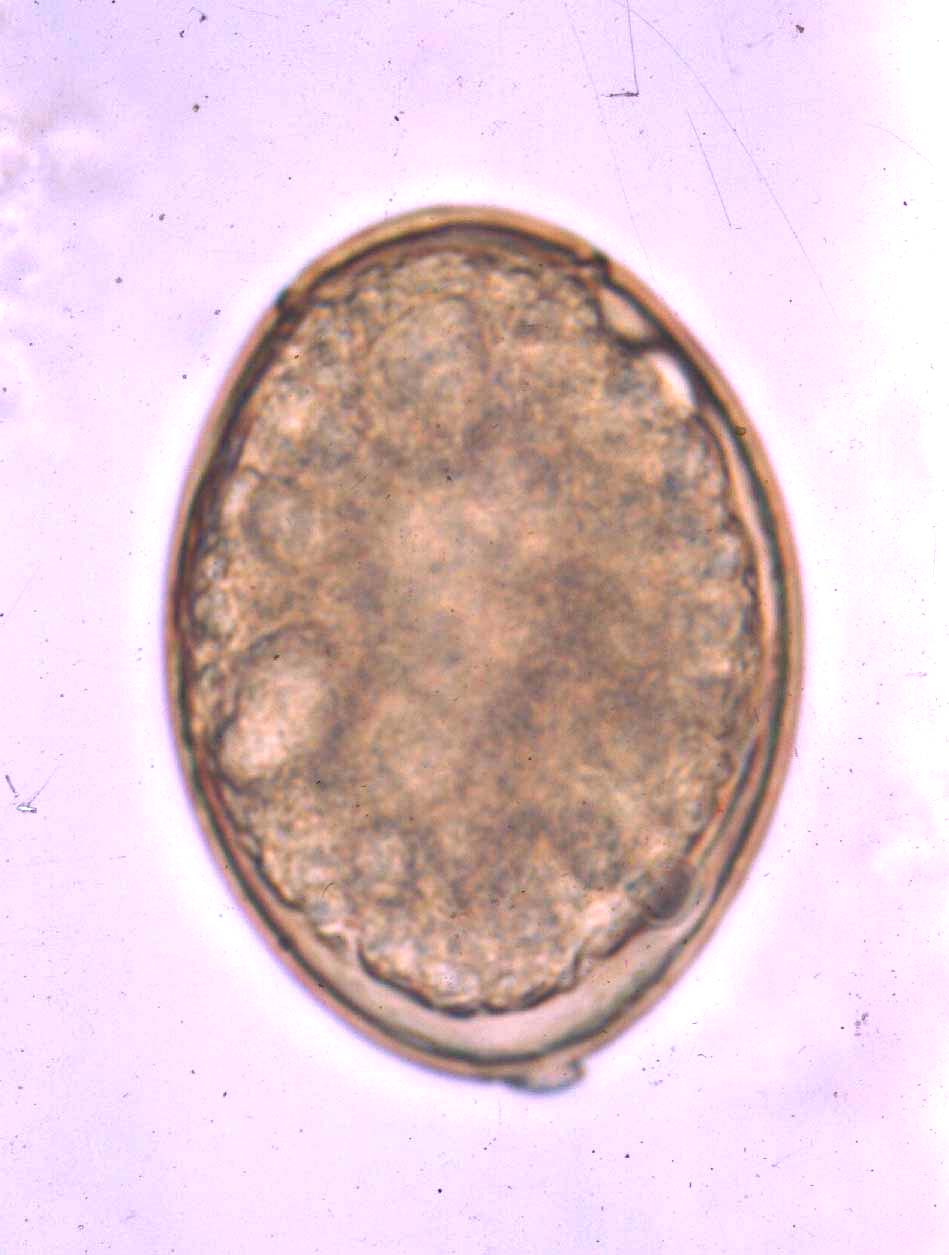

2Ascaris lumbricoides oeuf